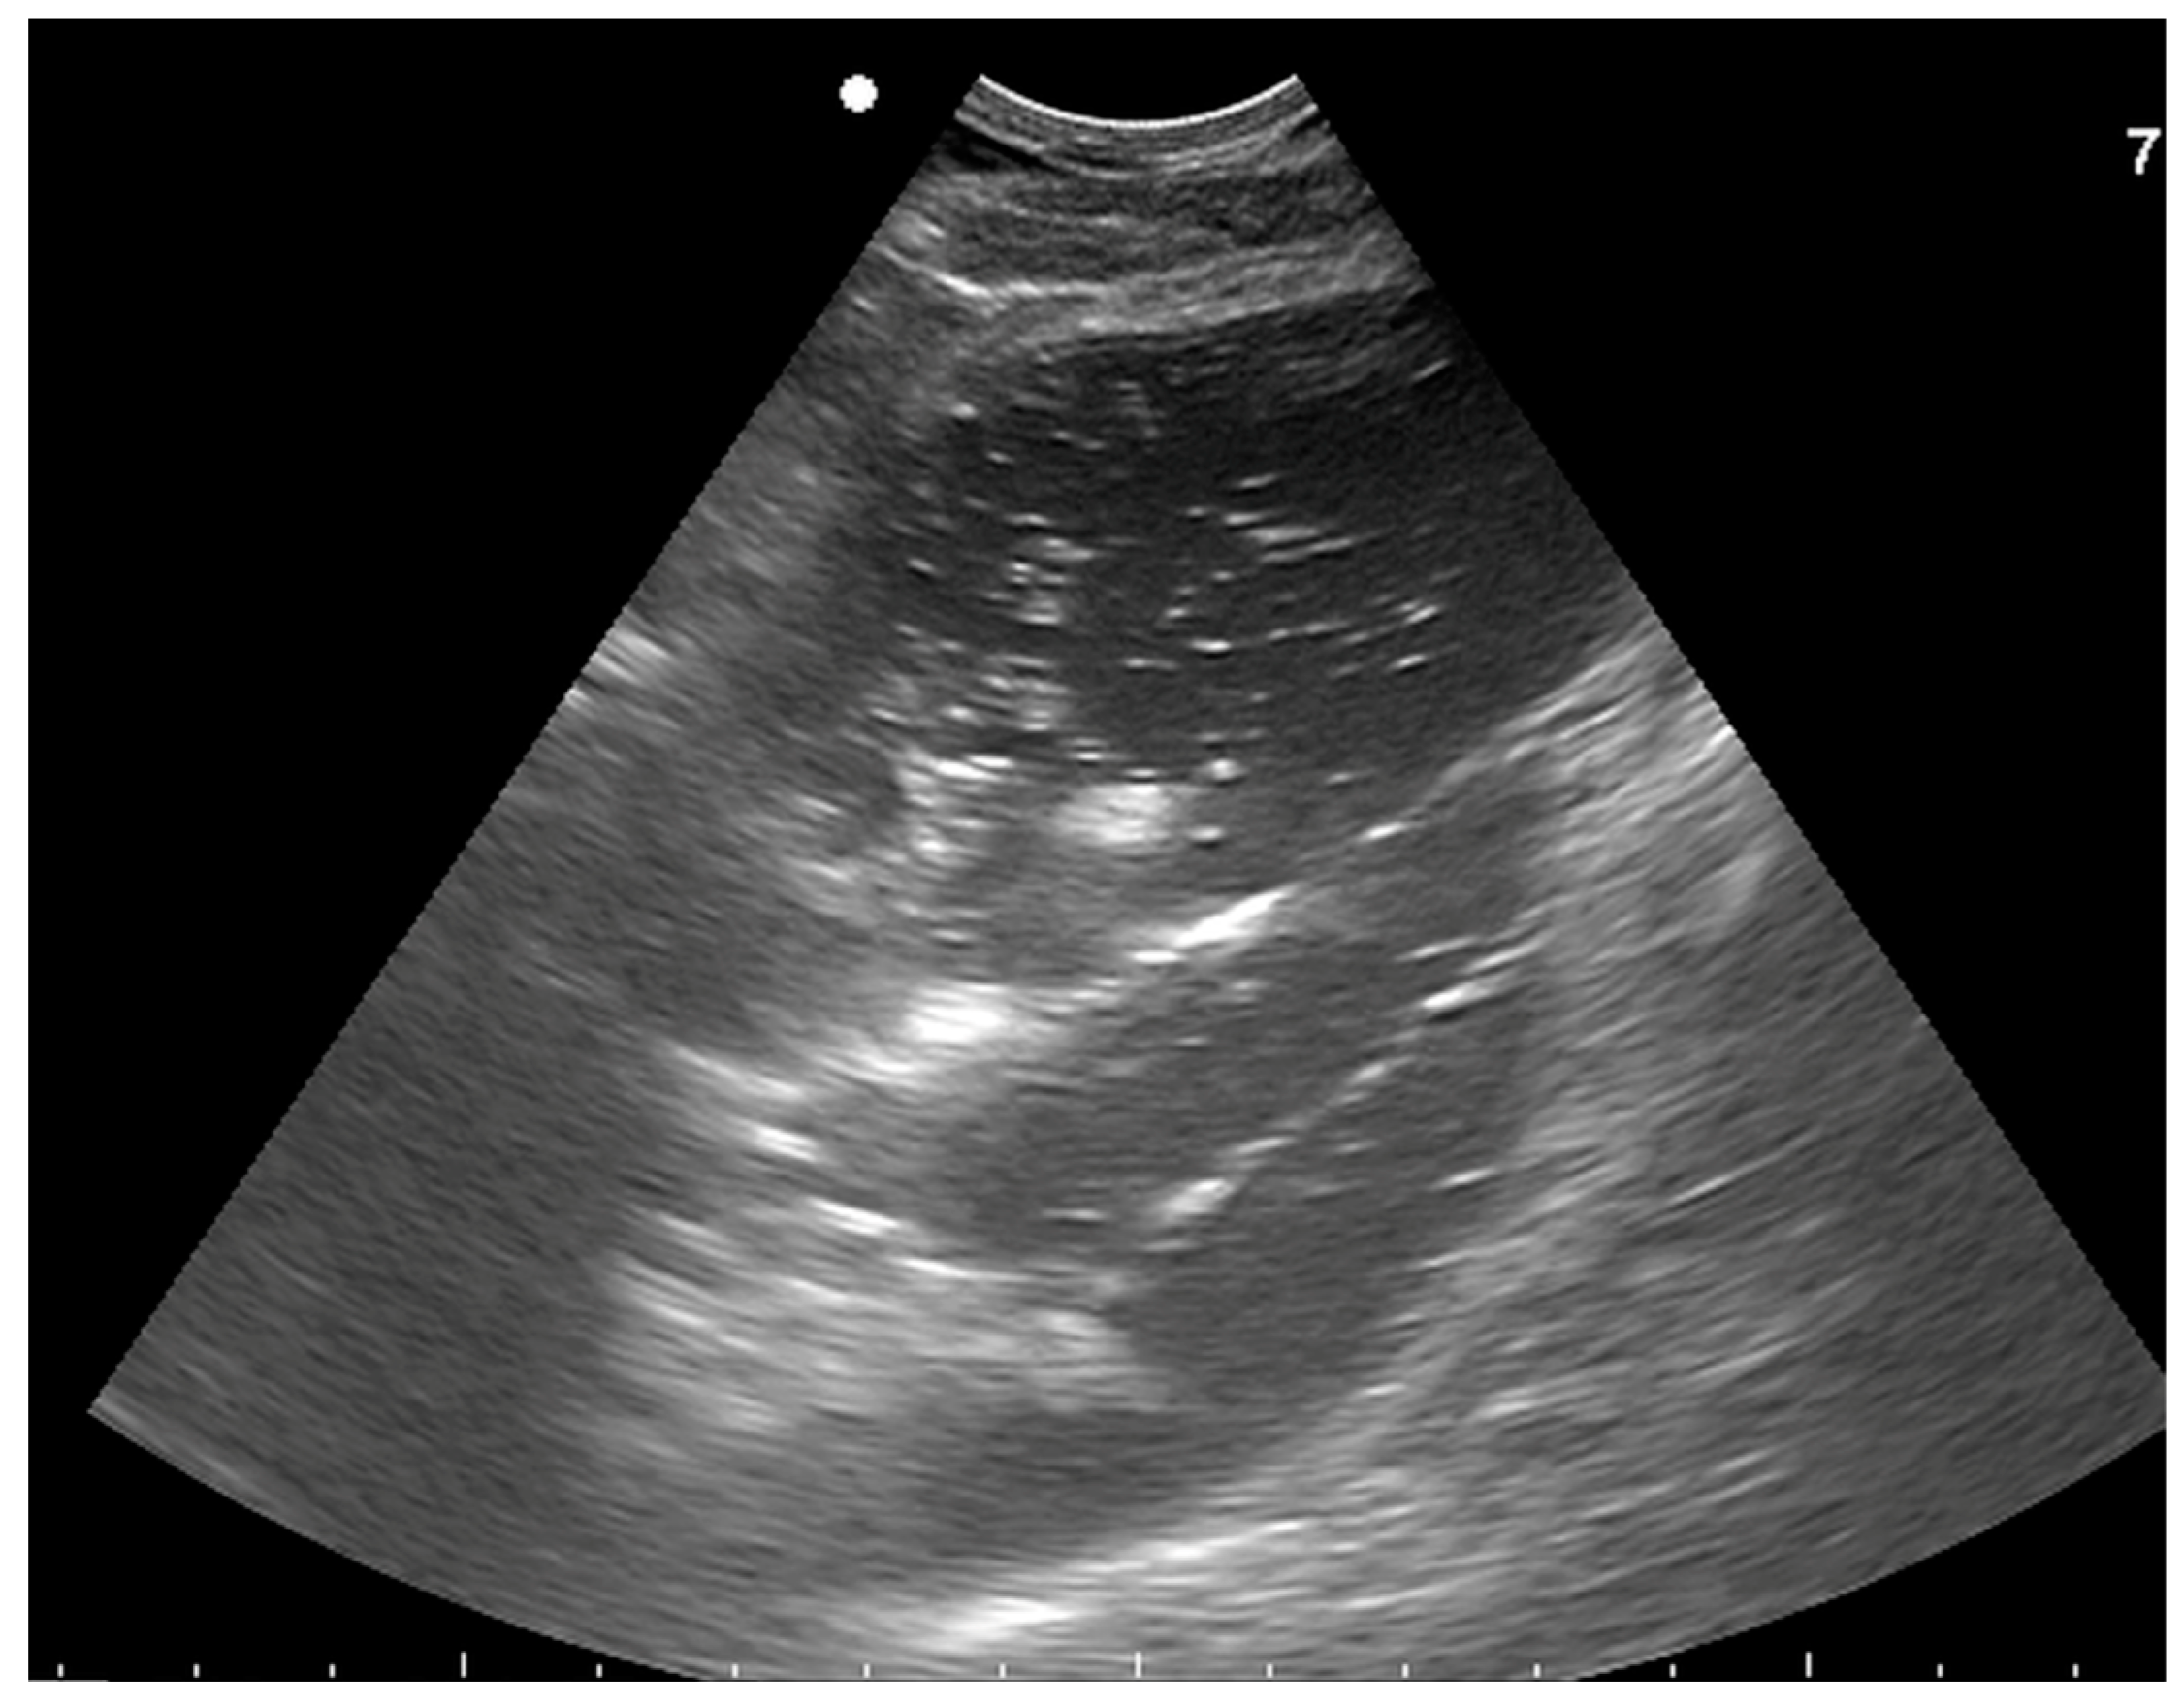

2.2. Ultrasound